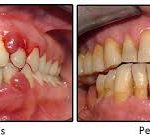

- Diş eti iltihabı (Gingivitis) ve periodontitis riskini artırır:

Sigara içenlerde diş eti hastalıklarının görülme sıklığı içmeyenlere göre çok daha yüksektir. Nikotin ve diğer kimyasallar, diş etlerindeki kan akışını azaltarak bağışıklık sisteminin yanıtını zayıflatır. Bu durum, bakteri plağının diş etine verdiği hasarın artmasına yol açar. - Diş eti çekilmesi (Recession) ve kemik kaybı:

Sigara, periodontal dokuların iyileşmesini engeller ve diş etinin dişten uzaklaşmasına sebep olur. Bu da diş köklerinin açığa çıkmasına ve diş kaybına zemin hazırlar. - Diş eti iltihabının belirtilerini gizleyebilir:

Sigara içenlerde kan akışının azalması nedeniyle diş etlerinde kızarıklık ve kanama daha az görülür. Bu, hastalığın daha geç fark edilmesine ve ilerlemesine neden olur.